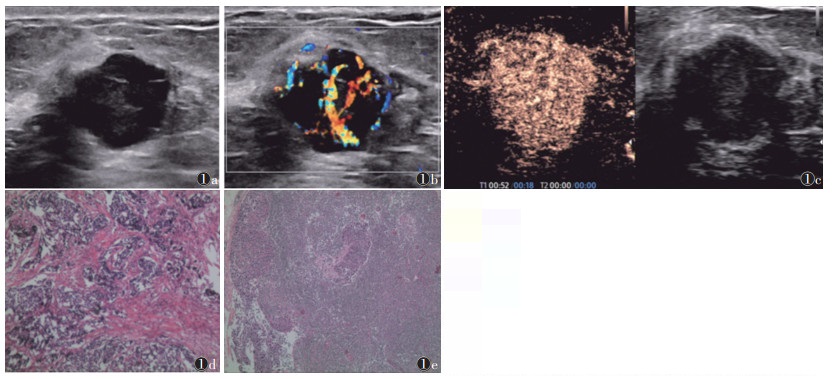

2.2 ALNM的单因素分析ALNM组血流分级多为Ⅱ~Ⅲ级,增强方向为向心性、边缘呈放射状增强、内部有滋养血管的比例均高于无ALNM组(均P<0.05);2组其他超声特征比较,差异均无统计学意义(均P>0.05)(表 1;图 1,2)。

| 注:患者,女,53岁。图1a为灰阶超声,示病灶呈低回声,内部回声不均匀,形态不规则,边缘不光整,可见微分叶及毛刺;图1b为彩色多普勒超声,示病灶内见丰富血流信号,血流分级Ⅲ级;图1c为超声造影,示病灶呈不均匀高增强,内见滋养血管,边缘不光整,见放射状血管,增强范围较二维图像扩大;图1d为术后病理,示浸润性导管癌(HE染色,高倍放大);图1e为淋巴结术后病理,示腋窝淋巴结转移(HE染色,低倍放大) 图 1 乳腺癌伴腋窝淋巴结转移典型病例的灰阶超声、彩色多普勒超声、超声造影及病理图像 |